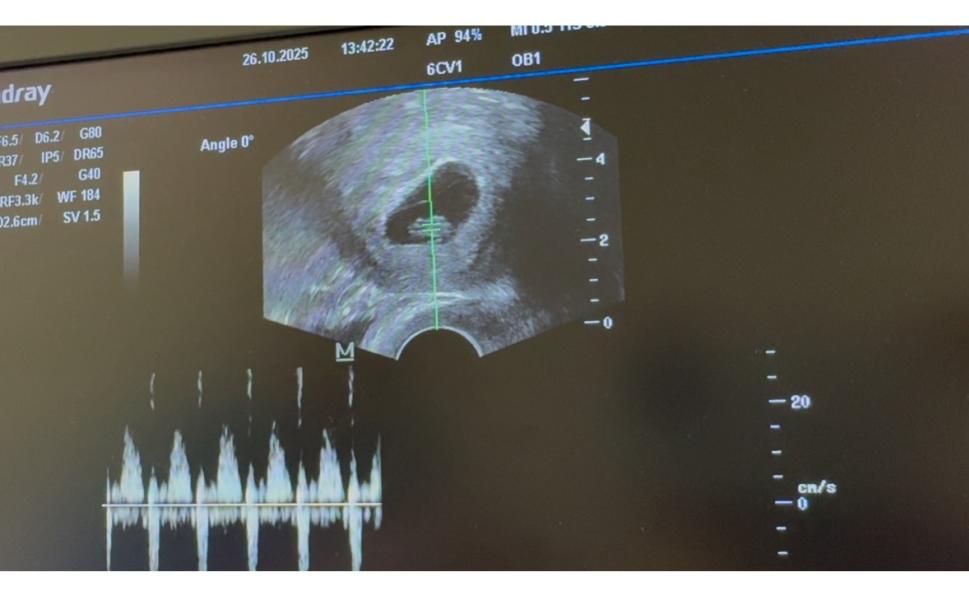

Сегодня слушали сердцебиение 💗

@sohruzausmonova, первый раз просто смотрели прикрепление на раннем сроке и второй прием назначили для просллушки сердца .